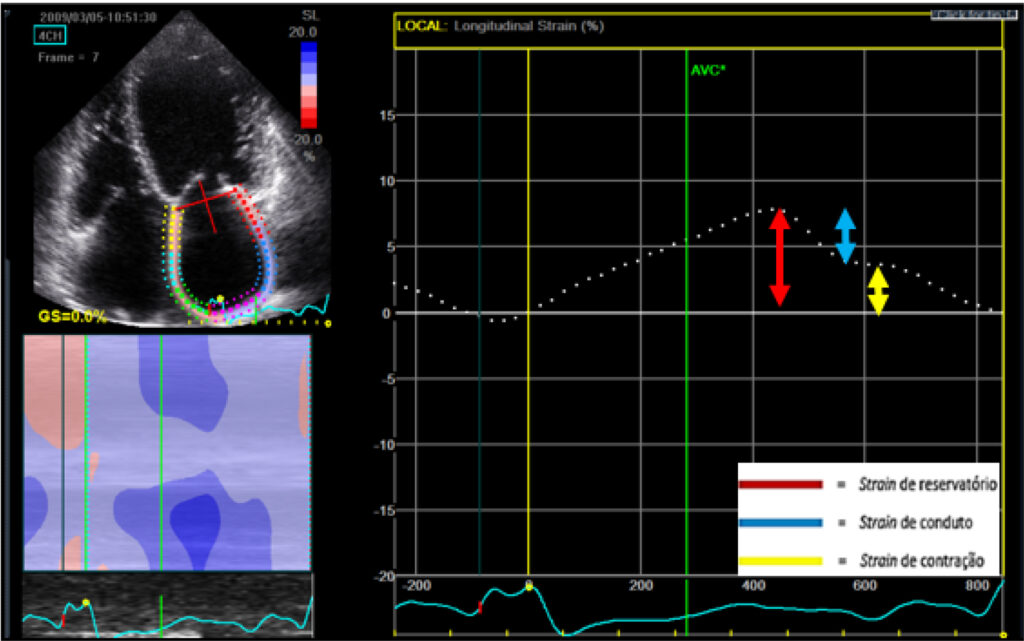

This cross-sectional observational study included 214 patients with DC, 46 without FMR (control group) and 168 with mild, moderate or severe FMR. An LAF analysis was performed by speckle tracking echocardiography (STE) and atrial volumetric variation.

LAF analyzed by STE by means of reservoir strain, conduit strain and active contraction strain was reduced in the sample, with values of 14.3%, 8.49% and 5.92%, respectively. FMR degree was significantly associated with reservoir strain (0.27 ± 0.16 versus 0.15 ± 0.09; p < 0.001) and contraction strain (19.2 ± 7.3 versus 11.2 ± 2.7; p < 0.001). FMR was also associated with a reduced LAF assessed by volumetric analysis: total atrial emptying fraction of 0.51 ± 0.13 versus 0.34 ± 0.11 and active atrial emptying fraction of 0 .27 ± 0.16 versus 0.15 ± 0.09 (p < 0.001).